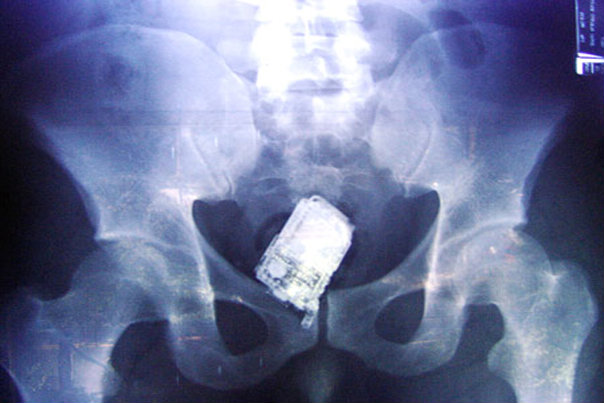

1. Rentgenska snimka nepoznatog datuma pokazuje mobilni telefon u donjim dijelovima probavnog trakta jednog zatvorenika iz Salvadora.